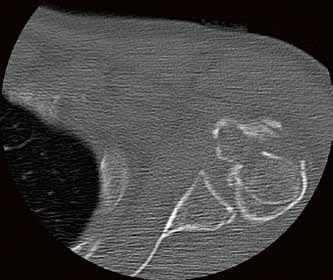

Die Klinik verfügt über 14 Computertomographen (CT), zwölf Magnetresonanztomographen (MRT) sowie zahlreiche Ultraschallgeräte. Allein am Campus Benjamin Franklin führen die Radiologen an sieben Tagen die Woche je zwischen 50 und 60 CT Untersuchungen täglich durch. Seit knapp drei Monaten steht ihnen dazu der neue 160-Schicht-Low-Dose-CT Aquilion PRIME zur Verfügung. Ein weiterer Aquilion PRIME sowie ein 640-Schicht-Volumen-CT Aquilion ONE ViSION EDITION wurden am Campus Mitte installiert. „Als wir nach einem neuen CT gesucht haben, war klar, dass dessen Ausstattung allen universitären diagnostischen Anforderungen gerecht werden muss", erklärt Dr. Stefan Niehues, Radiologe und Oberarzt der Klinik für Radiologie am Campus Benjamin Franklin.

„Mit dem neuen CT Aquilion PRIME können wir das komplette radiologische Spektrum der Charité abdecken. „Die gesamte Polytrauma-Diagnostik über die Akutversorgung bis hin zur Neuroradiologie und Diagnostik bei jungen Menschen führen wir mit dem Aquilion PRIME durch."

Neben der Rechnergeschwindigkeit lautet das Schlüsselwort bei dem neuen Gerät „Adaptive Iterative Dosis-Reduktion (AIDR 3D)". „Dieser mathematische Algorithmus erlaubt es uns, mit einem Bruchteil der Dosis zu arbeiten, die wir bisher für die erforderliche Bildqualität benötigt haben", weiß der Radiologe.

„Durch die Spitzentechnologie können wir bei gleich hoher Bildqualität die Dosis an Röntgenstrahlung bei vielen Untersuchungen auf ein Drittel reduzieren."